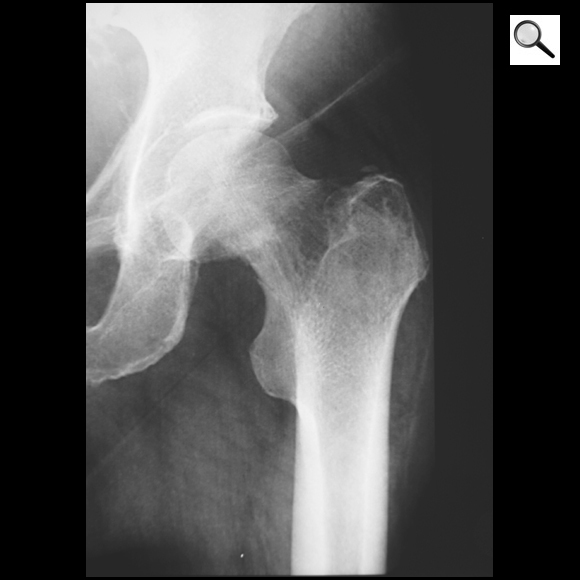

Quelle est la tumeur probable sachant qu’elle est maligne?

A

Tumeur épiphysaire à matrice cartilagineuse (pop corn) = chondrosarcome de l’extrémité sup du fémur